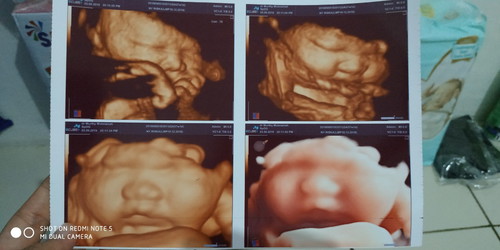

38 week

bun, kemaren aku usg babyku pipinya gembul gitu ? katanya beratnya udah 3.6kg ? biasanya pas lahir nanti lebih besar apa lebih kecil ya bun? aku pingin normal, tapi kalo babynya kegedean jadi worry juga karna hpl masih 2 minggu lagi takut babynya tambah besar lagi ☹️